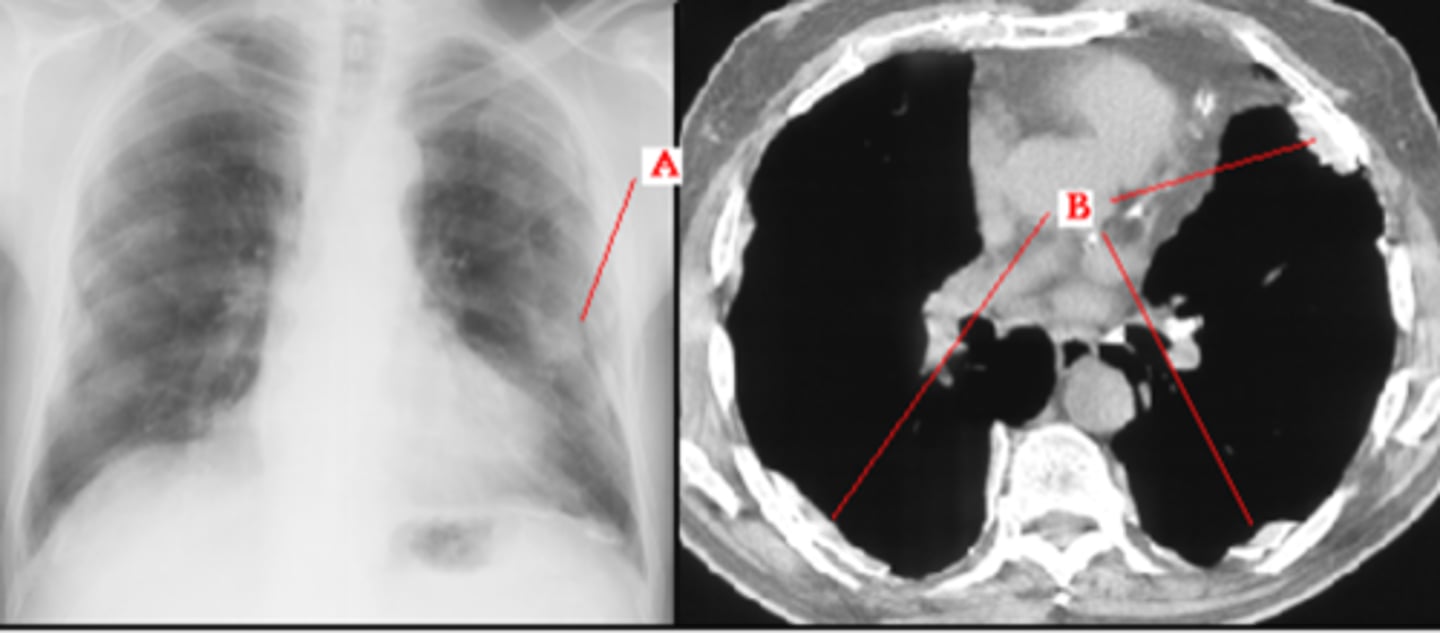

Pneumomediastinum (mediastinal emphysema)

knowt flashcard image

Pneumomediastinum